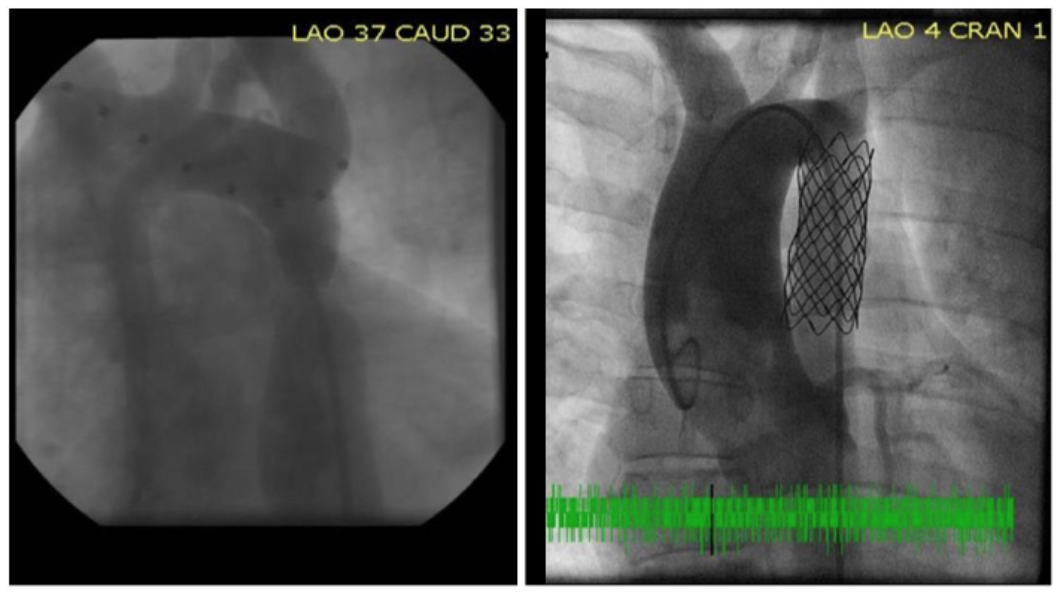

Measuring aortic diameter and volume. The study's primary outcome was anatomical changes in arch morphology evaluated as the difference between aortic dimensions before stent implantation and after stent implantation at 1-year follow-up. We first investigated the primary outcome through aortic diameter measurements using catheterization images at baseline and at the 1-year angiogram follow-up (Figure A in Supplemental material). An in situ 10 mm interval marker catheter was used for magnification correction. However, due to noncompatible angiographic angulations between studies, a number of paired acquisitions could not be used (Figure 1). Accordingly, to decrease the measurement error, aortic volumes, or the sum of cross-sectional disks obtained from non-invasive imaging (CT scans or MRI studies), were used.

Aortic diameter measurements. Average time from the procedure to first follow-up cardiac catheterization was 1.9 years (SD = 1.4 years). Twenty paired cardiac catheterizations were used to compare aortic diameters (paired pre- and post-operative catheterization image seen in Supplemental material, Figure C). No significant differences were found in baseline characteristics when comparing these 20 patients to the total sample (Supplemental material, Table B). Table 2 reports aortic diameter measurements of paired cardiac catheterizations normalized to BSA (cm/m2). A significant decrease in mean aortic diameter was observed in the aortic arch immediately proximal to the left carotid artery (LCA) origin (P=.024), the widest dilated area distal to the stenosis (P<.001), and a significant increase at the area of tightest stenosis (P<.001). A spaghetti plot of all paired aortic diameter changes for all 20 patients is shown in Figure 2.